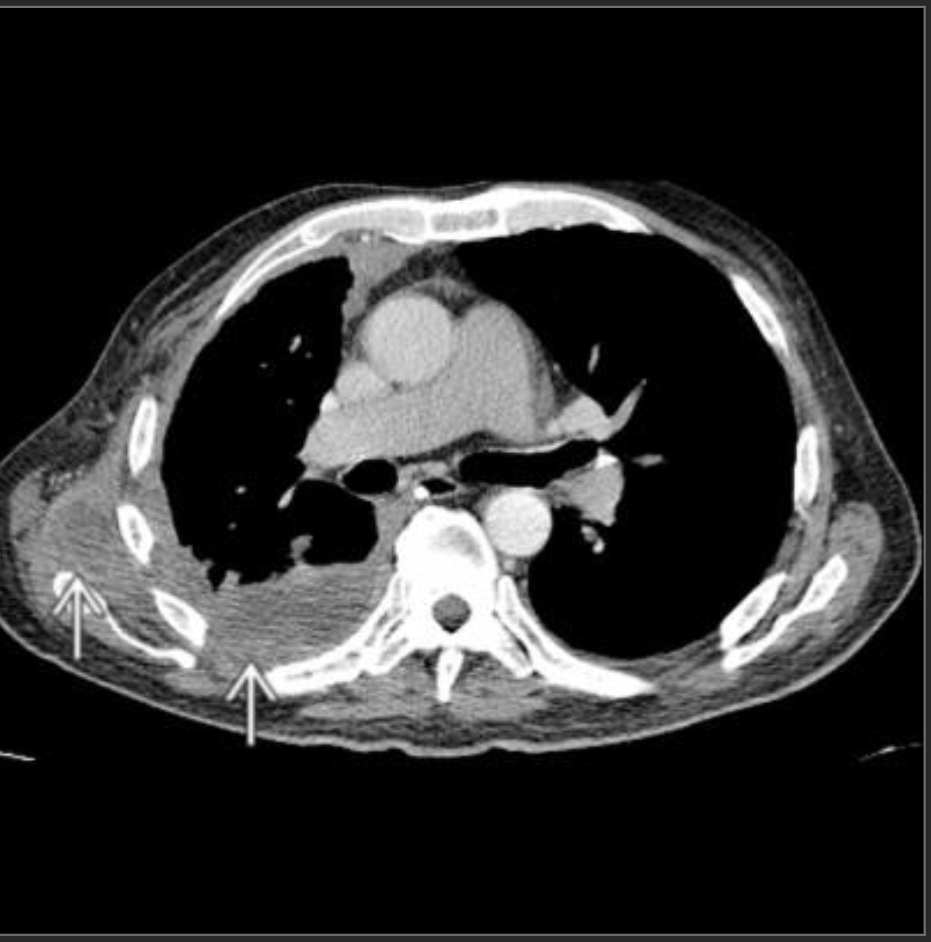

Empyema necessitans

chronic empyema attempting to decompress through the chest wall.

Common organisms include Tuberculosis, Actinomycosis, Staphylococcus, Aspergillosis, Mucormycosis, and Blastomycosis.

Look for loculated pleural fluid or mass with rib destruction.

Diagnosis = fine needle aspiration biopsy and microbiology.

Treatment = surgical drainage and antibiotics.